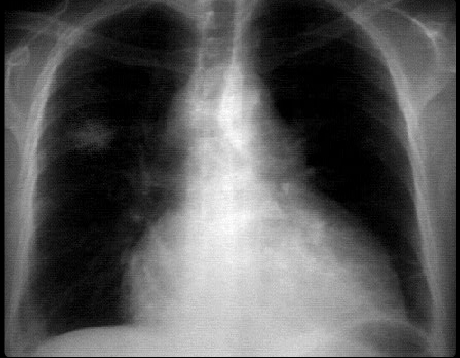

You are incorrect - the best interpretation of the chest X rays in this patient is pericardial calcification

Your choice: Lung mass and pericardial effusion

This chest X ray demonstrates a lung mass and pericardial effusion. The PA view demonstrates a non-calcified mass in the peripheral portion of the right upper lobe. The cardiopericardial silhouette is enlarged. Whether this is a pericardial effusion and/or cardiac enlargement would require additional imaging studies. This left hilum is also abnormal from either a mediastinal mass or an enlarged pulmonary artery. With the lung mass, the former is more likely.